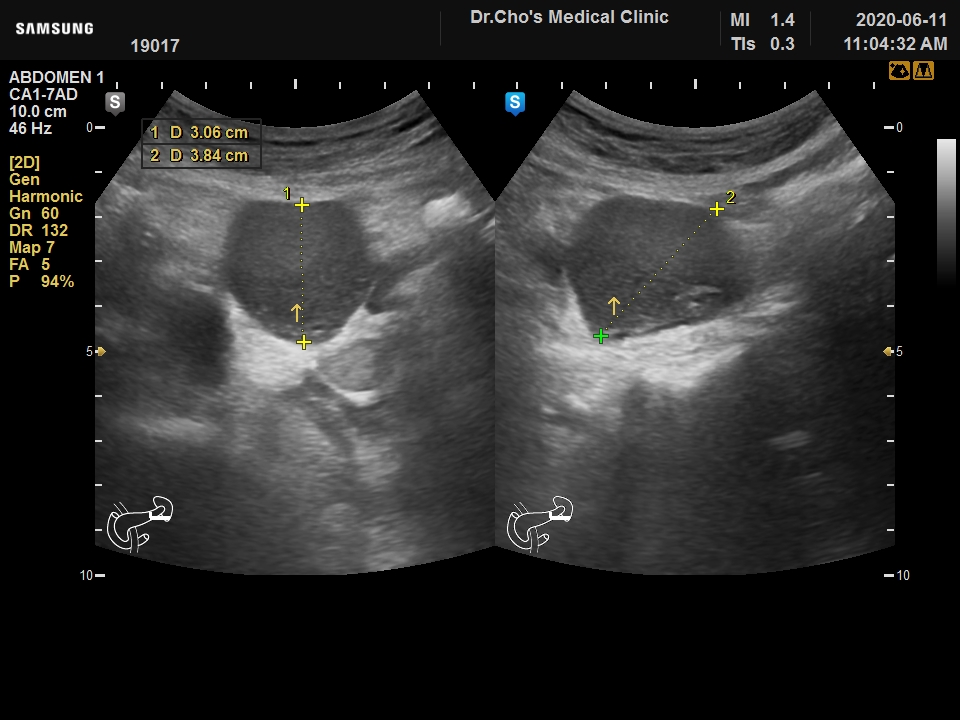

ÃÊÀ½ÆÄ°¶·¯¸®

ÃéÀå ³¶Á¾

¿ä·Î°á¼® ...